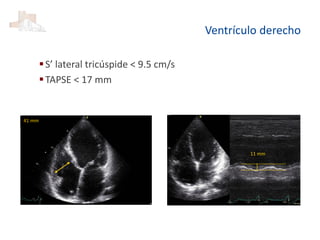

Ventrículo derecho

S’ lateral tricúspide < 9.5 cm/s

TAPSE < 17 mm

41 mm

11 mm

Ventrículo derecho S’ lateraltricúspide < 9.5 cm/s TAPSE < 17 mm 41 mm 11 mm